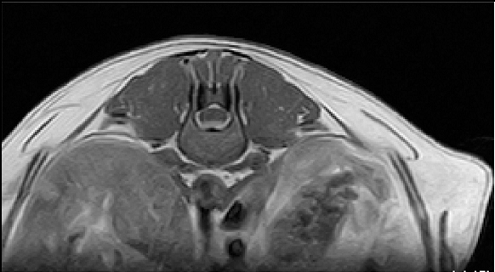

【画像診断】~ダックスフンド、雄10歳、グレート3の椎間板ヘルニア~

▲椎間板ヘルニアがあるMRI像、T13-L1の尾側像、造影後のT1強調画像(キャミックに依頼)

はい、たいへん有効です。その椎間板ヘルニアの起こっている部位や、左右どちらに起こっているか、その他の異常(合併症等)があるかもこの検査で調べます。脊椎の診断はMRI検査が最も理想的な検査法ですが、撮影時間や費用、設備の有無等に制約があるます。より実用的な検査としてはCTも良い検査法になりますが約15%でその部位に石灰化が起こってないとわらない場合がありますが、そんな場合は造影をすれば判定できます。MRIの場合、椎間板の変性はT2強調像、矢状断面像で最も良く観察、でき脊髄腫瘍、椎体腫瘍等、脊髄髄内の検出にも理想的な検査です。多くの腫瘍はT1強調像では脊髄と比較すると等信号から低信号にT2強調像では高信号となります。